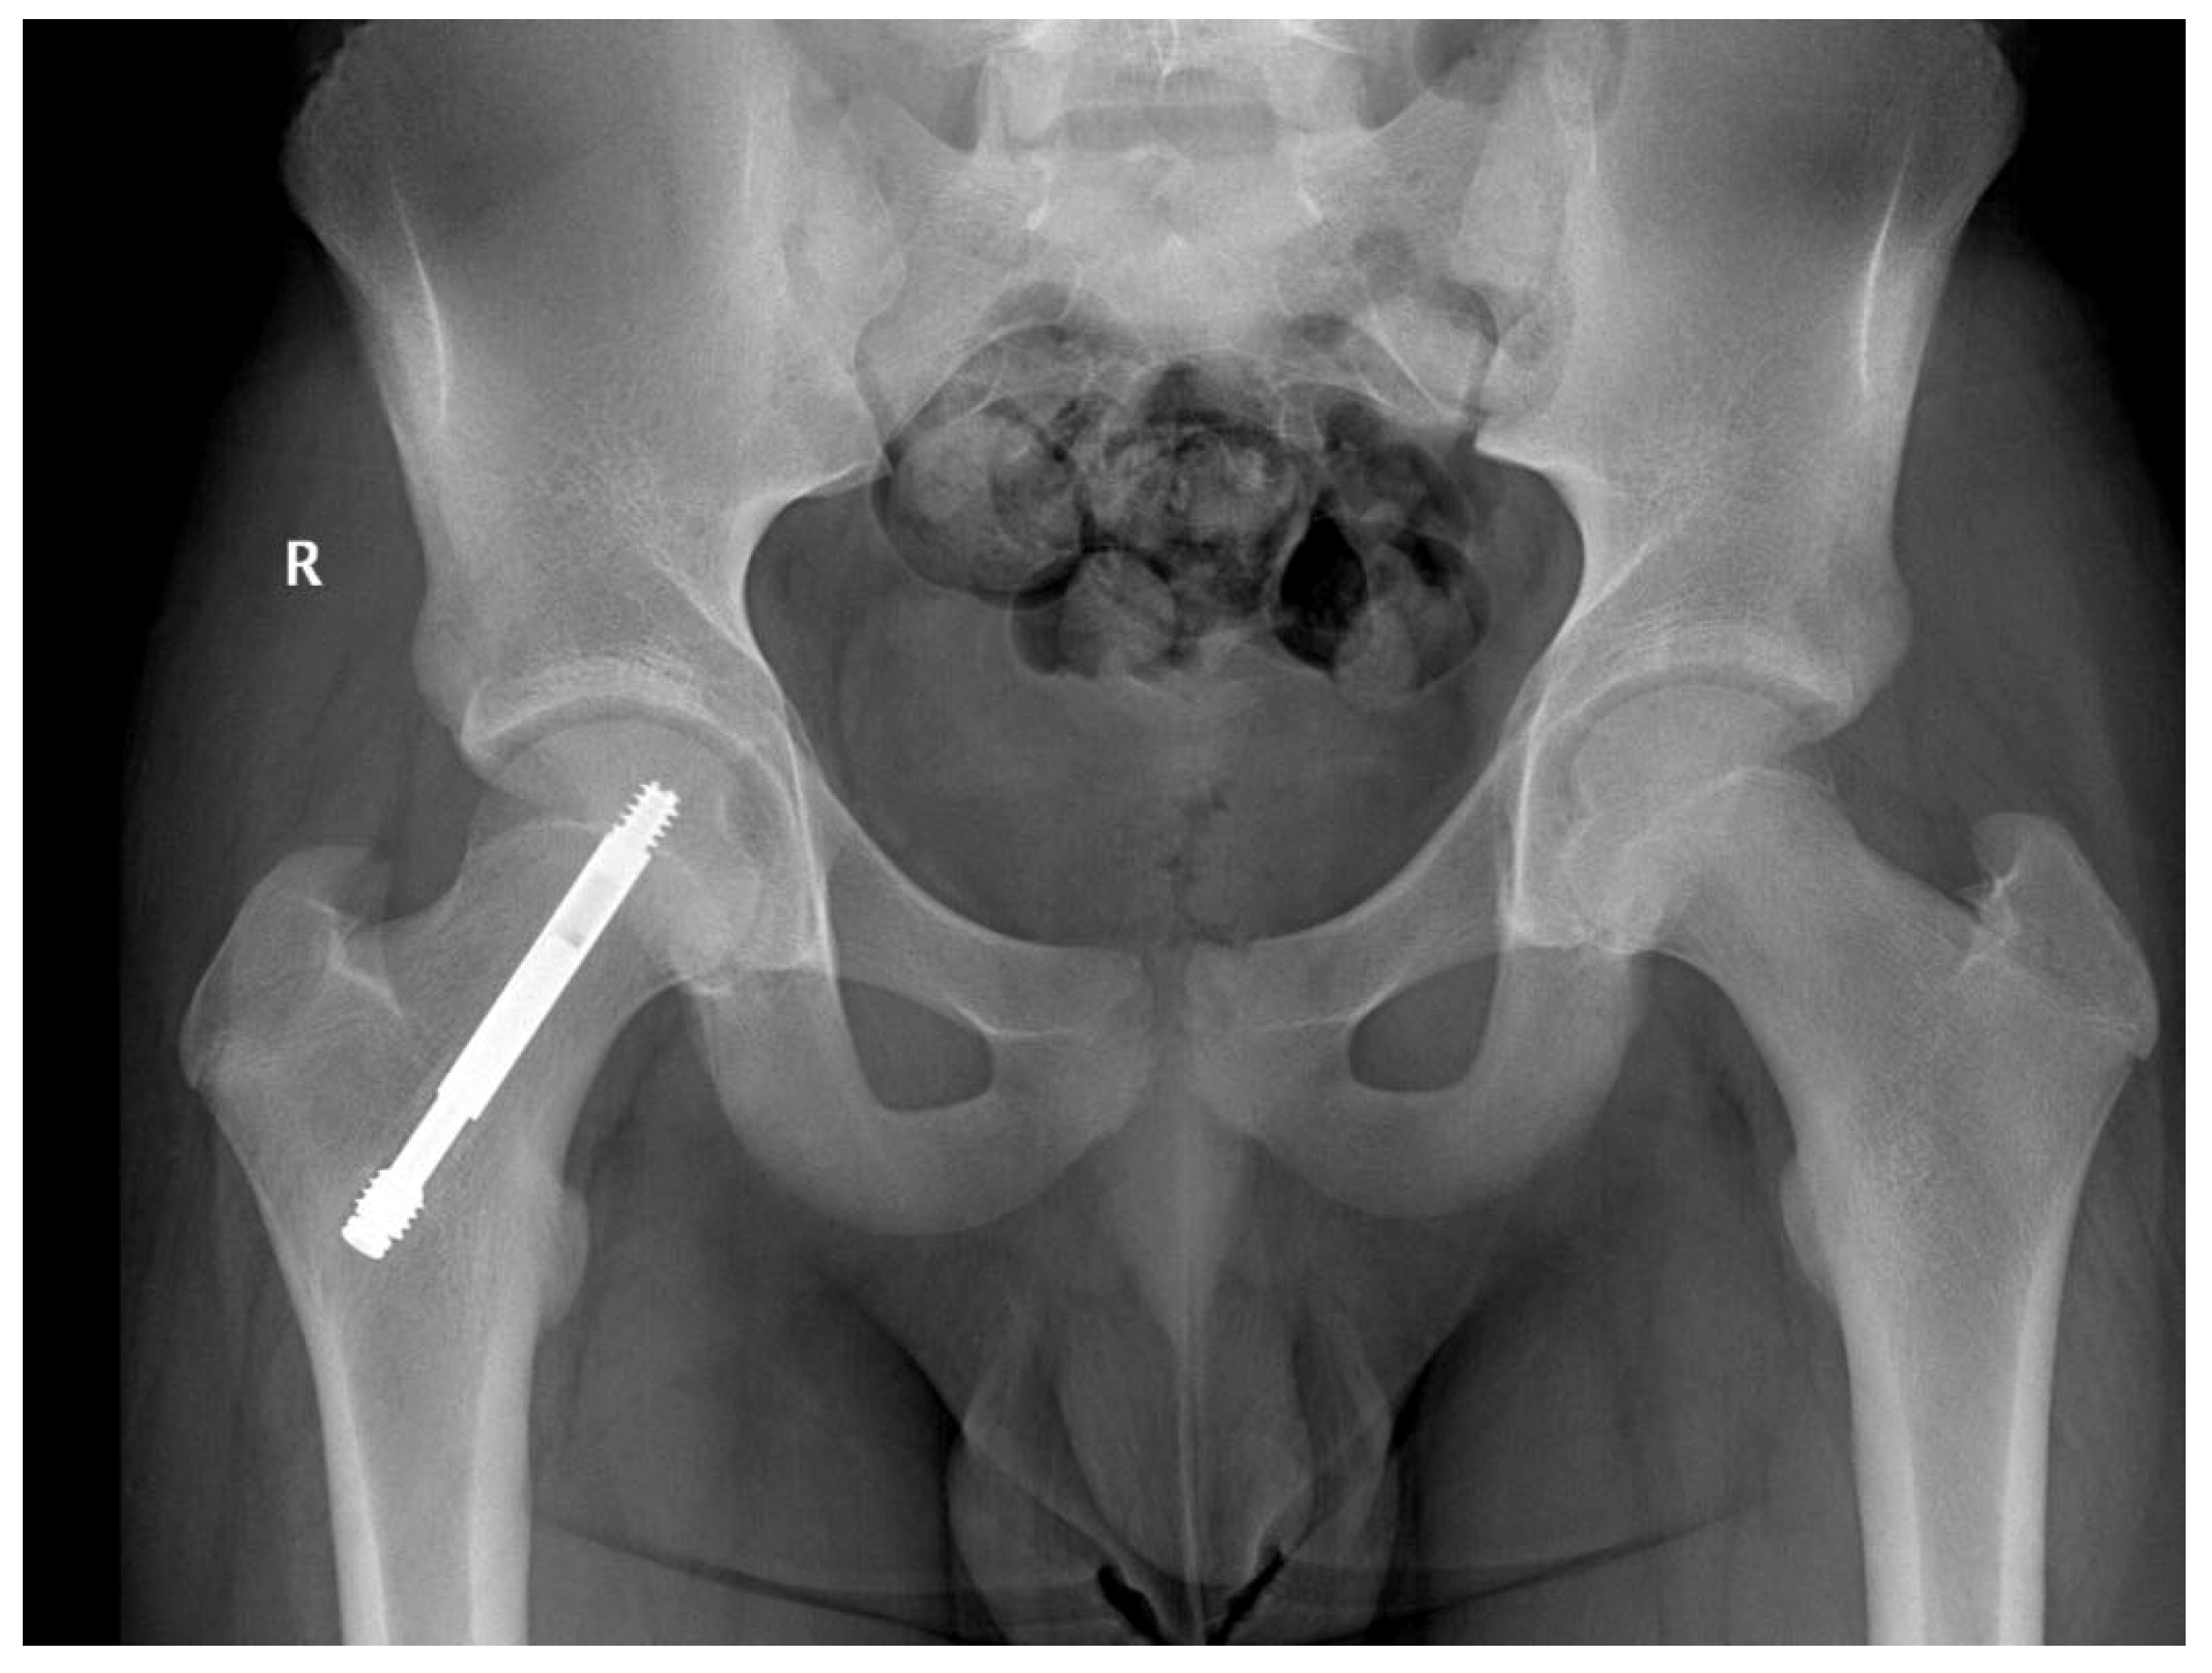

In one case, no lengthening of the screw was noticed 12 months after surgery, but with further follow-ups, the screw extended 15 mm after 3 years Figure 3. The follow-up should be extended to more years depending on the age and growth potential of the patient.

Figure 3.

Male patient, 11 years old at time of surgery, screw telescoped at 36 months follow-up; no length discrepancies noted.